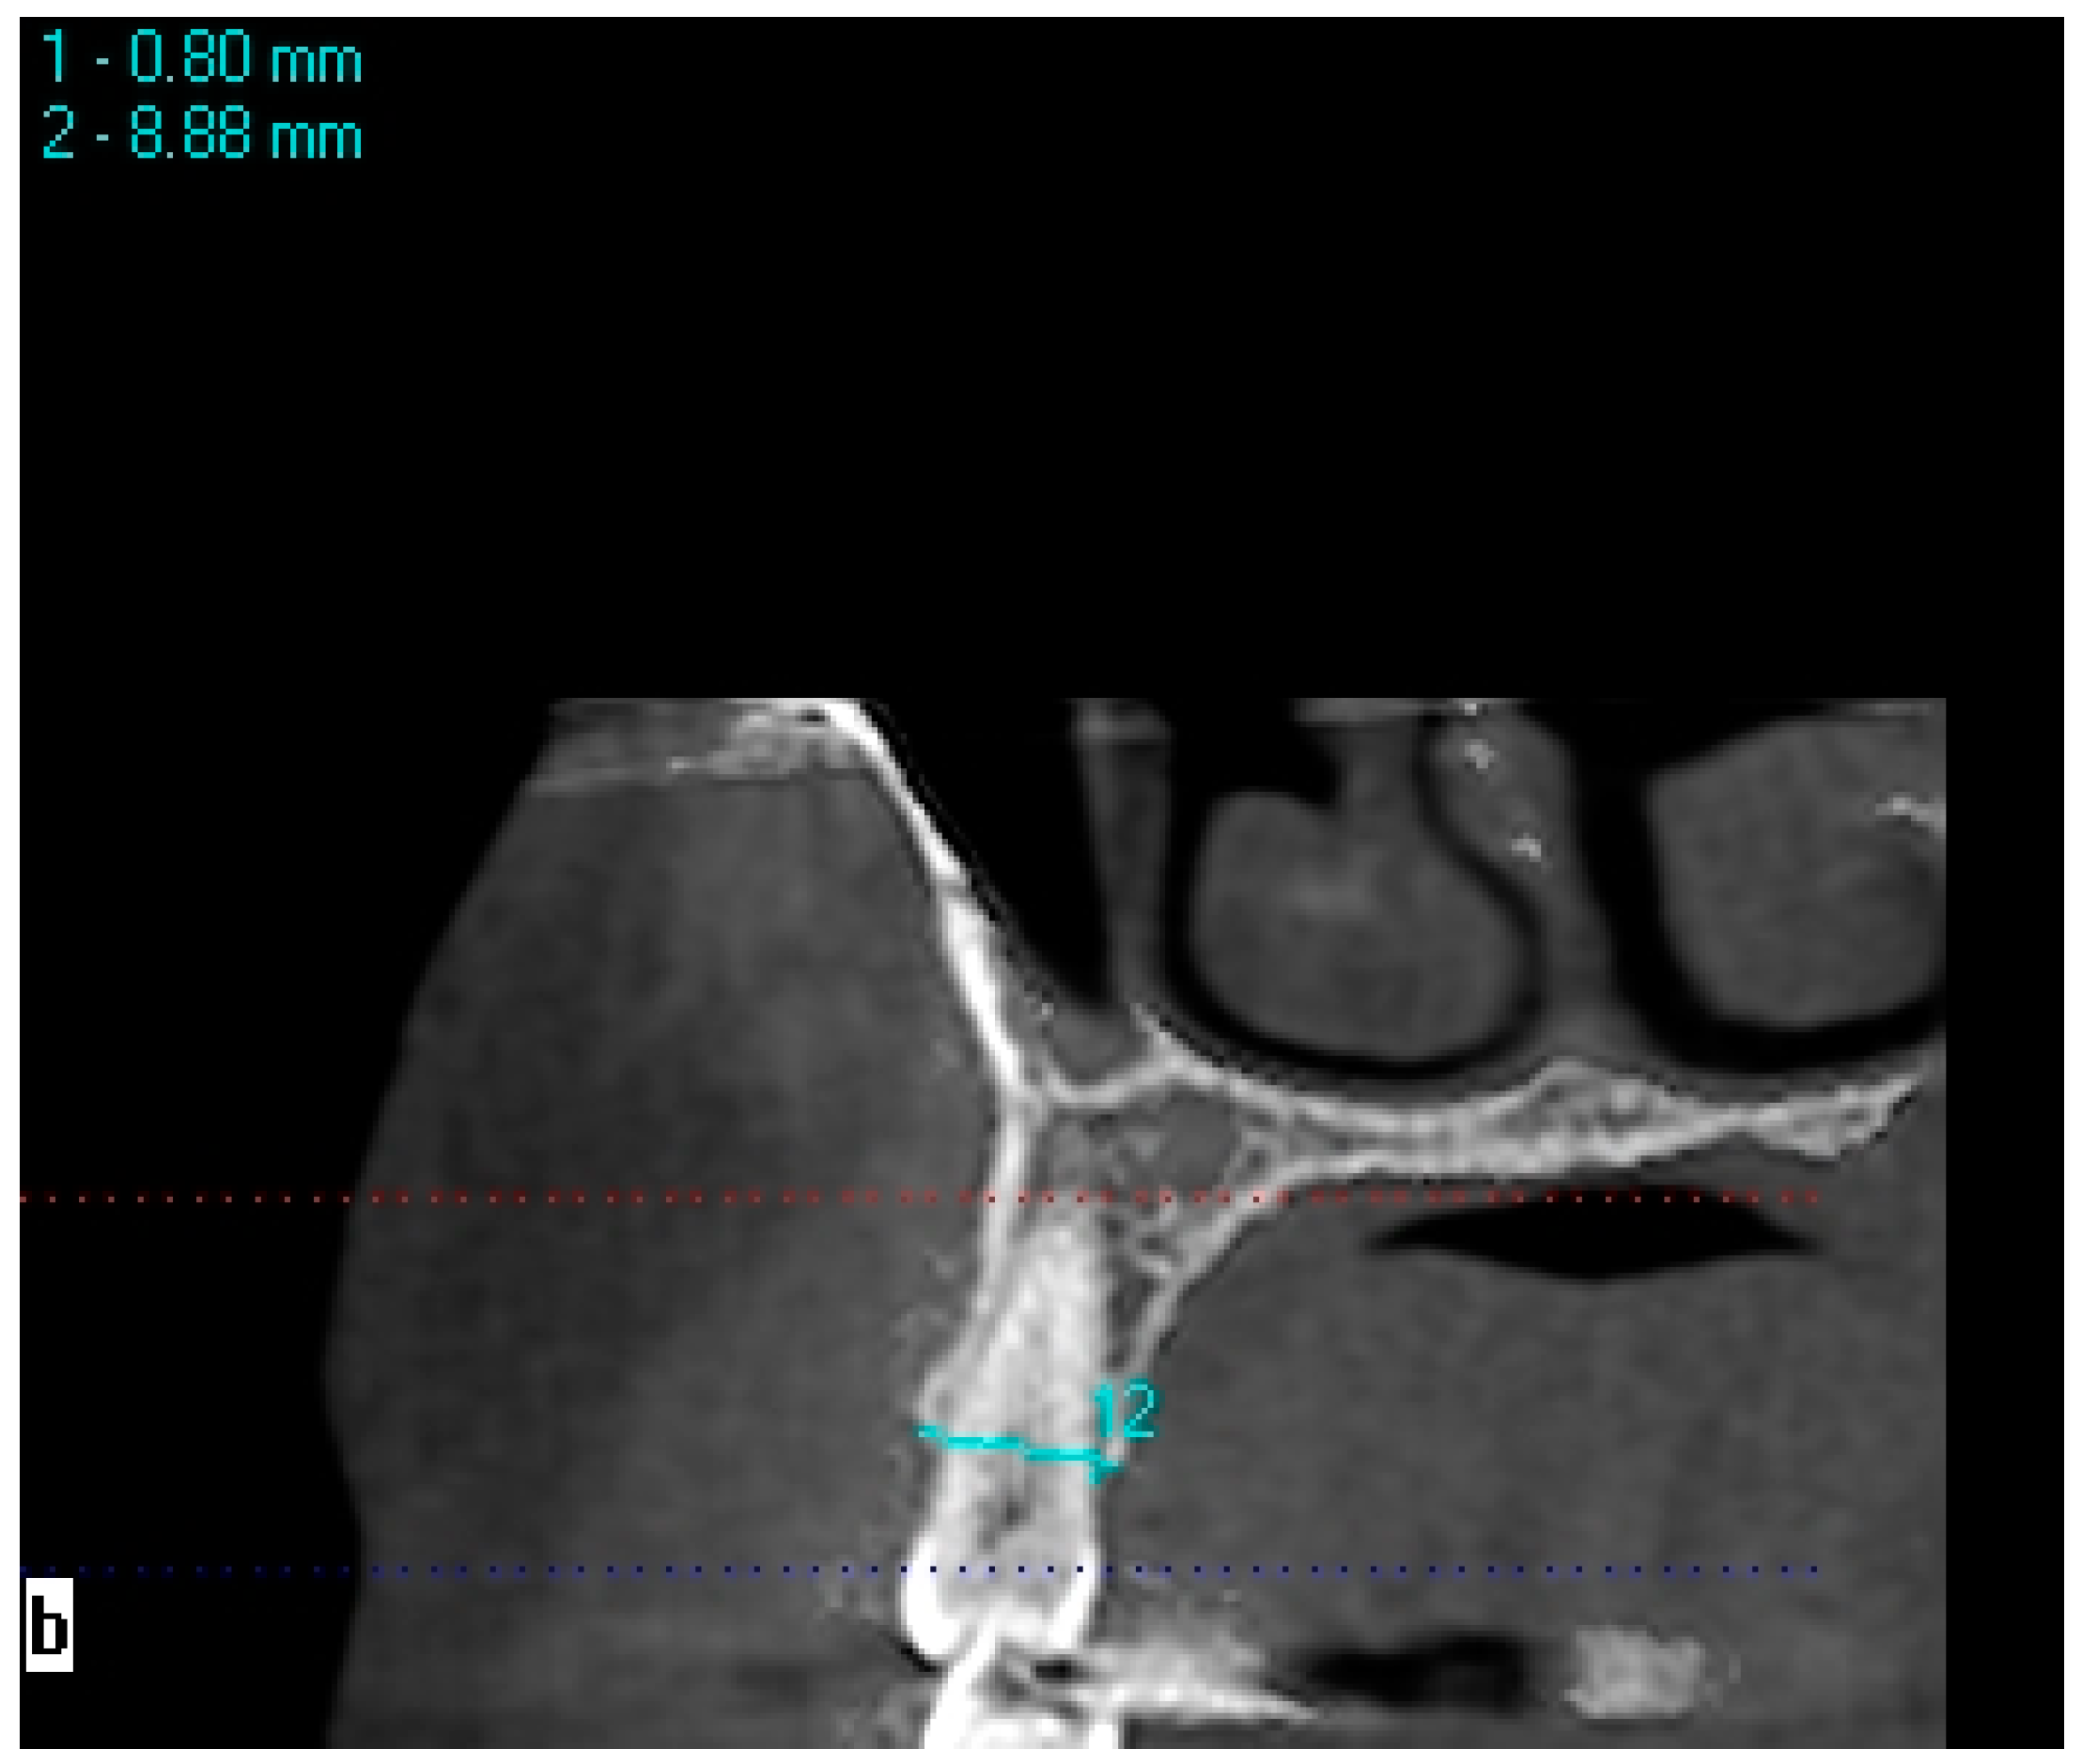

Bone measurements in areas with one missing tooth were made on 1.2 mm thick cross-sectional CBCT images obtained using the KaVo eXamVision (KaVo Dental GmbH, Biberach, Germany) program. Bone width was measured at the midpoint of the mesiodistal width of the edentulous region, 0.8 mm below the ridge crest, on the line connecting the vestibule/palatal and buccal/lingual walls (Figure 1). Bone width measurements at 2.8, 4.8, and 6.8 mm depths were performed following the same protocol as the bone width measurements performed at a 0.8 mm depth. The horizontal and vertical lines at 0.8 mm were used as the reference for the calculation of the depths. The protocol for edentulous crest measurements was applied in the same way for symmetrical toothed side measurements. Bone width measurements of symmetrical teeth were made with reference to the line that passes 0.8 mm below the lower crest of one of the buccal/vestibule and lingual/palatal bone walls (Figure 2). Bone heights were obtained through linear measurement of the distance between the reference point at the crest (the midpoint of the line at which bone width measurements were made) and the mandibular canal, maxillary sinus, mental foramen, and nasal floor. Intra-examiner reliability was calculated to assess the reliability of the measurements. The measurements in this study were performed by a single investigator specializing in oral and maxillofacial radiology. The second measurements were performed 4 weeks after the first measurement.

Figure 1. Measurement of bone width in the edentulous left second premolar area.